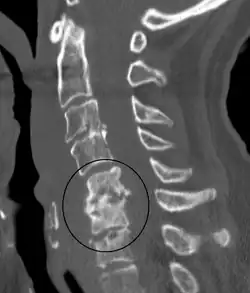

There is debate as to the cause, although hematogenous seeding of the offending organism is favored as well as direct spread. Spontaneous discitis is usually from hematologic spread from a urinary or respiratory infection while discitis from a post-operative complication usually involves skin flora such as staph aureus. It can be caused due to spinal tuberculosis and spread along spinal ligament to involve the adjacent anterior vertebral bodies, causing angulation of the vertebrae with subsequent kyphosis.[7] The cause may be aseptic.[8]

Diagnosis is usually apparent on MRI, although plain X-rays and CT examinations can be suggestive. The MRI will reveal air changes in the disc and possibly even external involvement involving the bone or epidural regions. A biopsy may be performed and helps with diagnosis in some cases but often an organism is not obtained. C-reactive protein levels and ESR levels will be elevated and are useful for treatment. The white blood cell count may be normal.[5][6]